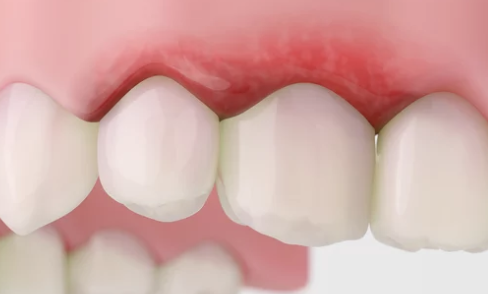

📌 레이저 치은 성형술

- 잇몸 가장자리를 정리하고 자극을 줄여 치유 유도

- 초경도 퇴축 및 염증이 있는 경우에 적합

- 통증 적고 회복 빠름, 단 퇴축된 잇몸 복원에는 한계가 있음